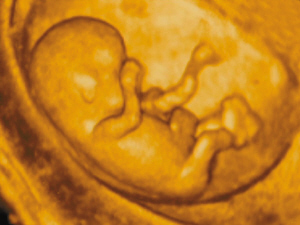

2、四维彩超

是目前先进的彩超检查设备,可以观察胎儿动态图像,能够全方位的胎儿的在子宫内的发育情况,并且能为胎儿是否存在先天性体表畸形和先天性心脏疾病提供准确的科学依据。>>>四维彩超检查的内容有几项呢?问问在线专家

美国GEVolusonE8四维彩超利用二维原理观测胎儿的组织结构,测量出胎儿头部身体的长度,内脏、骨骼的大小和形态,以及是否有畸形,同时能直观、立体的观察和显示人体器官的动态和三维结构,通过四维(全方位)立体成像,清晰并动态记录宝宝在子宫内的活动和成长历程,让爸爸妈妈享受与宝宝的第一次约会。